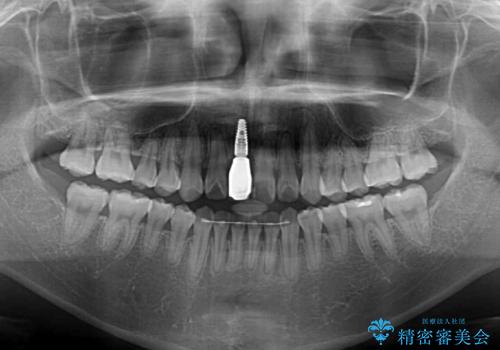

- 中学生の頃にぶつけた前歯に不格好なクラウンが装着されており、出っ歯な印象になっていることを気にして来院された患者様です。

ぶつけてしまった歯は保存が困難な状況であったので抜歯をし、ワイヤー矯正により歯列を整えつつ前歯の突出感を解消することとしました。

矯正治療後にはインプラント補綴治療を行うこととしました。

前歯の補綴治療はインプラントかブリッジかで悩んでいました。

周りの歯にむし歯がないため、インプラントがお勧めとなりますが、事故による骨欠損が大きく、歯肉ラインを整えるのが困難という問題がありました。